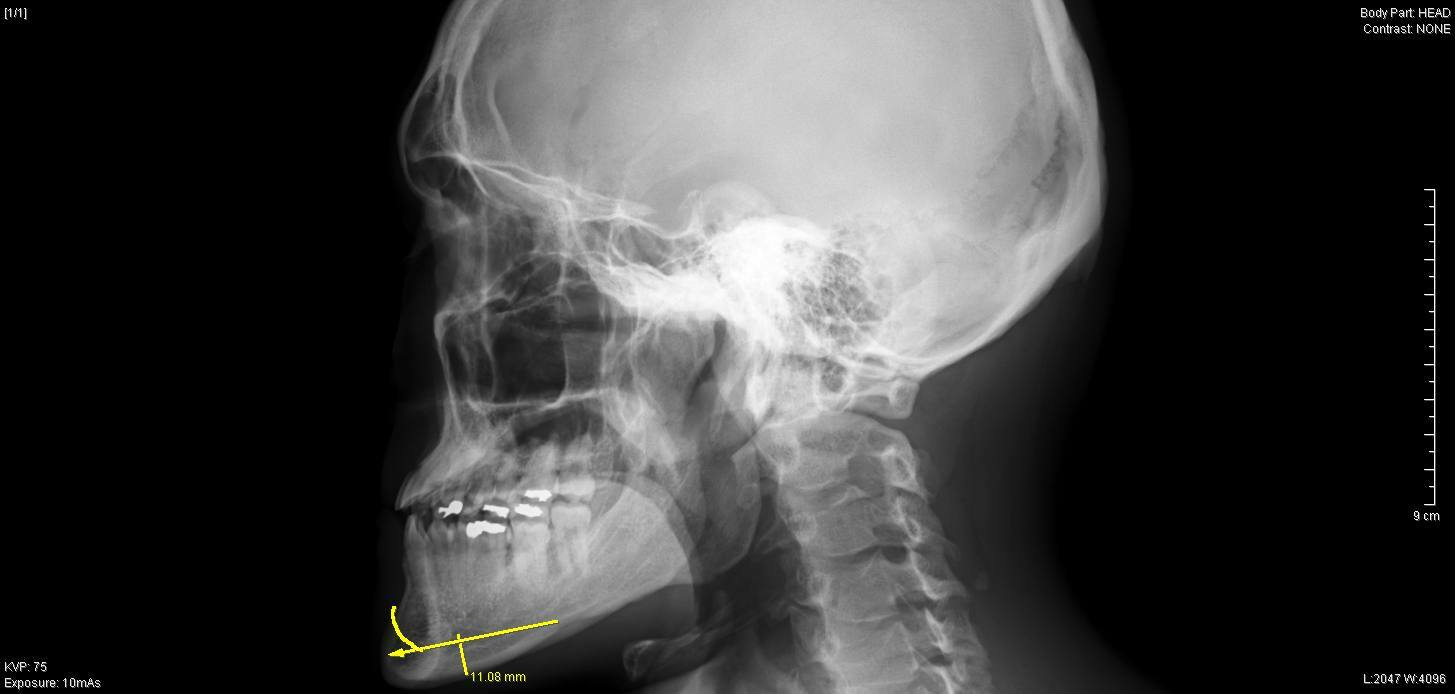

【骨切り手術前 左横】

レントゲンでは、上下方向の切除幅は約1cm、

それに加えEラインを考慮して、

右側 最大 10mm

左側 最大 9mm

先端部 7mm